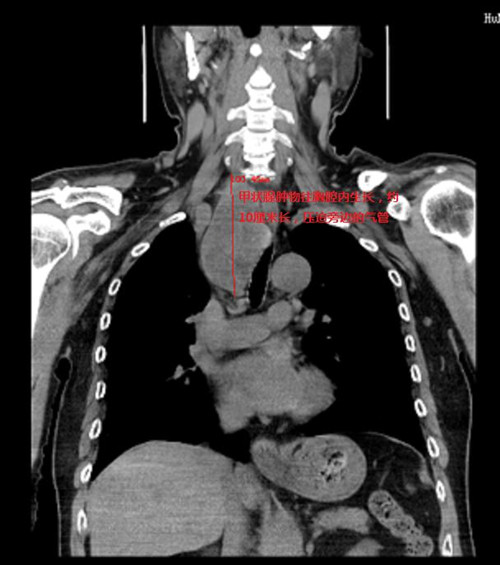

66岁的周嗲嗲家住马王堆,因气促咳嗽在捷克论坛 呼吸五科住院,胸部CT检查发现在右肺下叶有一个约鹌鹑蛋大小结节,同时在纵膈发现一巨大肿物压迫气管引起狭窄,经胸外科会诊,右肺下叶结节肺癌的可能性非常大,纵膈肿物是颈部甲状腺肿瘤往胸腔内长压迫气管,两个问题都要手术治疗。

恰逢2021年12月31日胸外二科在马王堆院区新开科,周嗲嗲从呼吸五科转到胸外二科。传统的胸骨后甲状腺肿物切除有可能要正中劈开胸骨,创伤非常大。为了尽可能减少手术对病人带来的创伤,周亚夫主任与乳甲外科、麻醉科、手术室开展术前讨论,制定最微创的手术方案。

麻醉科巧妙地用热水泡软双腔气管导管顺利通过气管狭窄处,是手术得以顺利实施的前提;胸外科在侧胸壁用一个仅3厘米的小切口完成单孔胸腔镜下右肺下叶切除及淋巴结清扫,同时将胸腔内胸骨后的甲状腺肿瘤完全游离松解,最后乳甲外科通过颈部小切口轻松取出胸骨后巨大甲状腺肿。手术时间短,术中出血少,手术后患者恢复良好,第二天就下床活动,轻松自如。